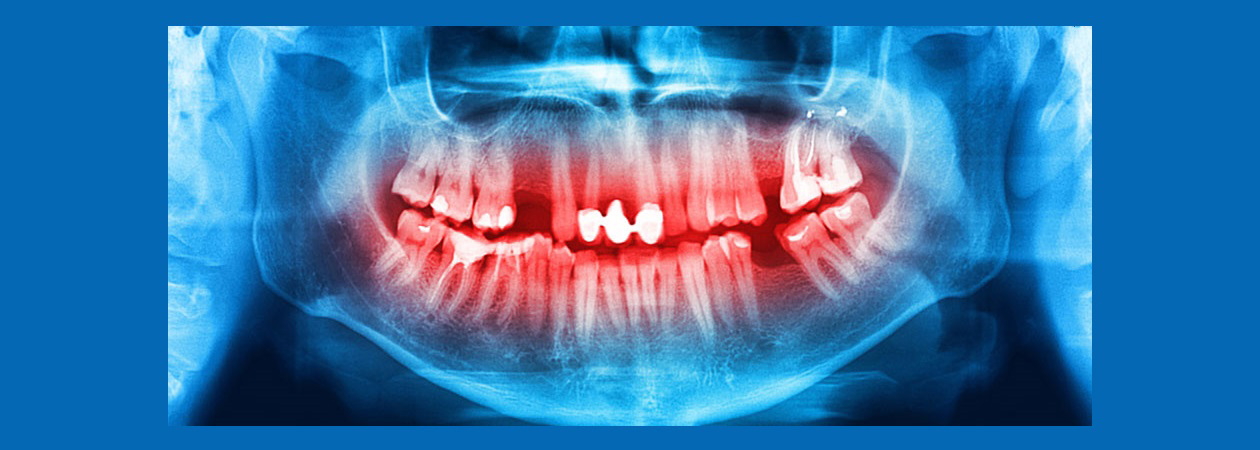

کیست

پاتولوژی، کیست